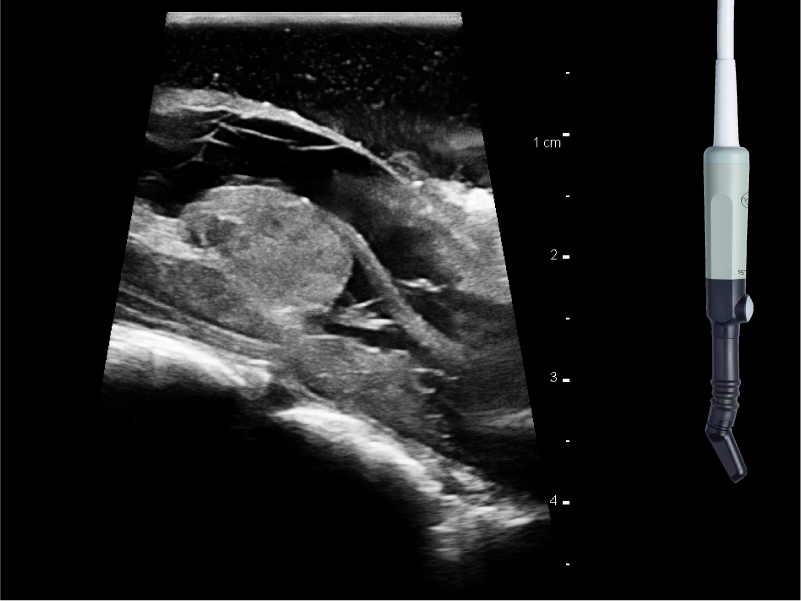

REAL-TIME VISUALIZATION HAS NEVER LOOKED THIS GOOD

- Enhanced Visualization: Improved algorithms for greater details around lesion borders, and automated high-resolution image settings.

- Neurosurgeon Control: Remote control and Smart Button™ on sterilizable transducers allow neurosurgeon control of the image in the sterile field.